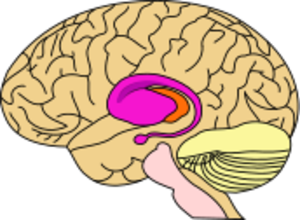

مرض هنتنجتونHuntington's disease هو اضطراب وراثي شديد في الجهاز العصبي. ويتسبب هذا المرض في تدمير خلايا الدماغ، كما يتسبب في حدوث حركات لا إرادية للجسم إلى جانب اضطراب عقلي تعقبه الوفاة. وهذا الاضطراب يصيب الناس من كلا الجنسين بصرف النظر عن العرق البشري. وأخذ هذا المرض اسمه من اسم أول من اكتشفه وهو جورج هنتنجتون الطبيب الأمريكي الذي كان أول من وصف هذا المرض في عام 1872م. وكانت هذه الحالة أصلا تسمى رَقَاص هنتنجتون.

وقد يكون أول الأعراض الجسمانية لهذا المرض تثاقلاً في الحركة أو عدم الحركة مطلقاً. ثم تبدأ بعد ذلك عضلات الوجه والأيدي في الارتعاش. وكلما زادت شدة المرض ازداد الانقباض العضلي اللا إرادي، وقد يصيب هذا الانقباض عضلات الجسم كلها. وبذلك يرتعش الرأس والكتفان والذراعان والساقان بطريقة غير إرادية. وعندما يسير المريض تتداخل الحركات الإرادية وغير الإرادية للجسم لينتج عنها ترنح في الجسم وخطوات تشبه إيقاع الرقص. وتشمل الأعراض العقلية المبكرة لهذا المرض الغباء، وتبلد الحسّ، وسرعة التهيج والتأثر، والإهمال في الهندام والمظهر الشخصي. ثم يعمل المرض على التدمير التدريجي لذكاء المريض ولذاكرته. وعندئذ قد يزداد المرض العقلي شدة.

وقد يفقد المريض أخيراً كل تحكم في العضلات وفي القدرة العقلية. وقد تحدث الوفاة نتيجة الالتهاب الرئوي أو الأزمة القلبية أو أي مضاعفات لهذا المرض.

التغيرات الخلوية بسبب mHTT

التغيرات الكبرى بسبب mHTT